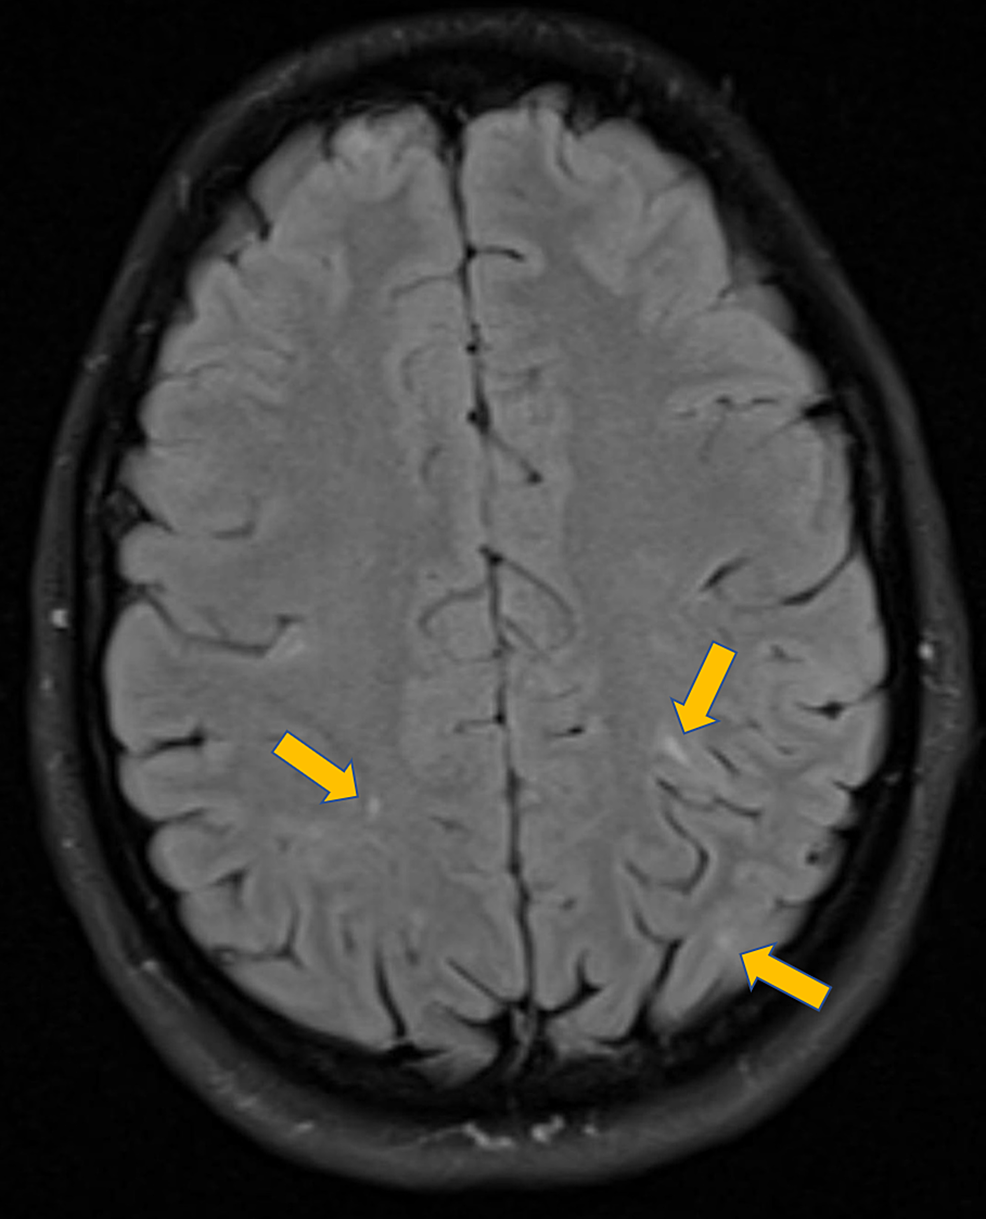

TUBEROUS SCLEROSIS IN A CHILD WITH CORTICAL AND SUBCORTICAL TUBERS(BLUE Tubers On The Brain They are found on the surface of the brain sitting within normal tissue. Cortical tubers are best visualized using mri of the brain. Tubers are disorganised areas of the brain that contain abnormal, large brain cells. The cortical tuber (from which tsc was originally named) is a disorganized area of the. There are three main anatomical features associated with tsc. Tubers On The Brain.

T2W MR images of brain showing multiple cortical tubers and calcified Tubers On The Brain Tuberous sclerosis (ts) growths, called tubers, are often found growing inside of the brain and retinal area of the eye. Tubers are disorganised areas of the brain that contain abnormal, large brain cells. The cortical tuber (from which tsc was originally named) is a disorganized area of the. These hard ‘lumps’ are the reason for the. Cortical tubers are best. Tubers On The Brain.